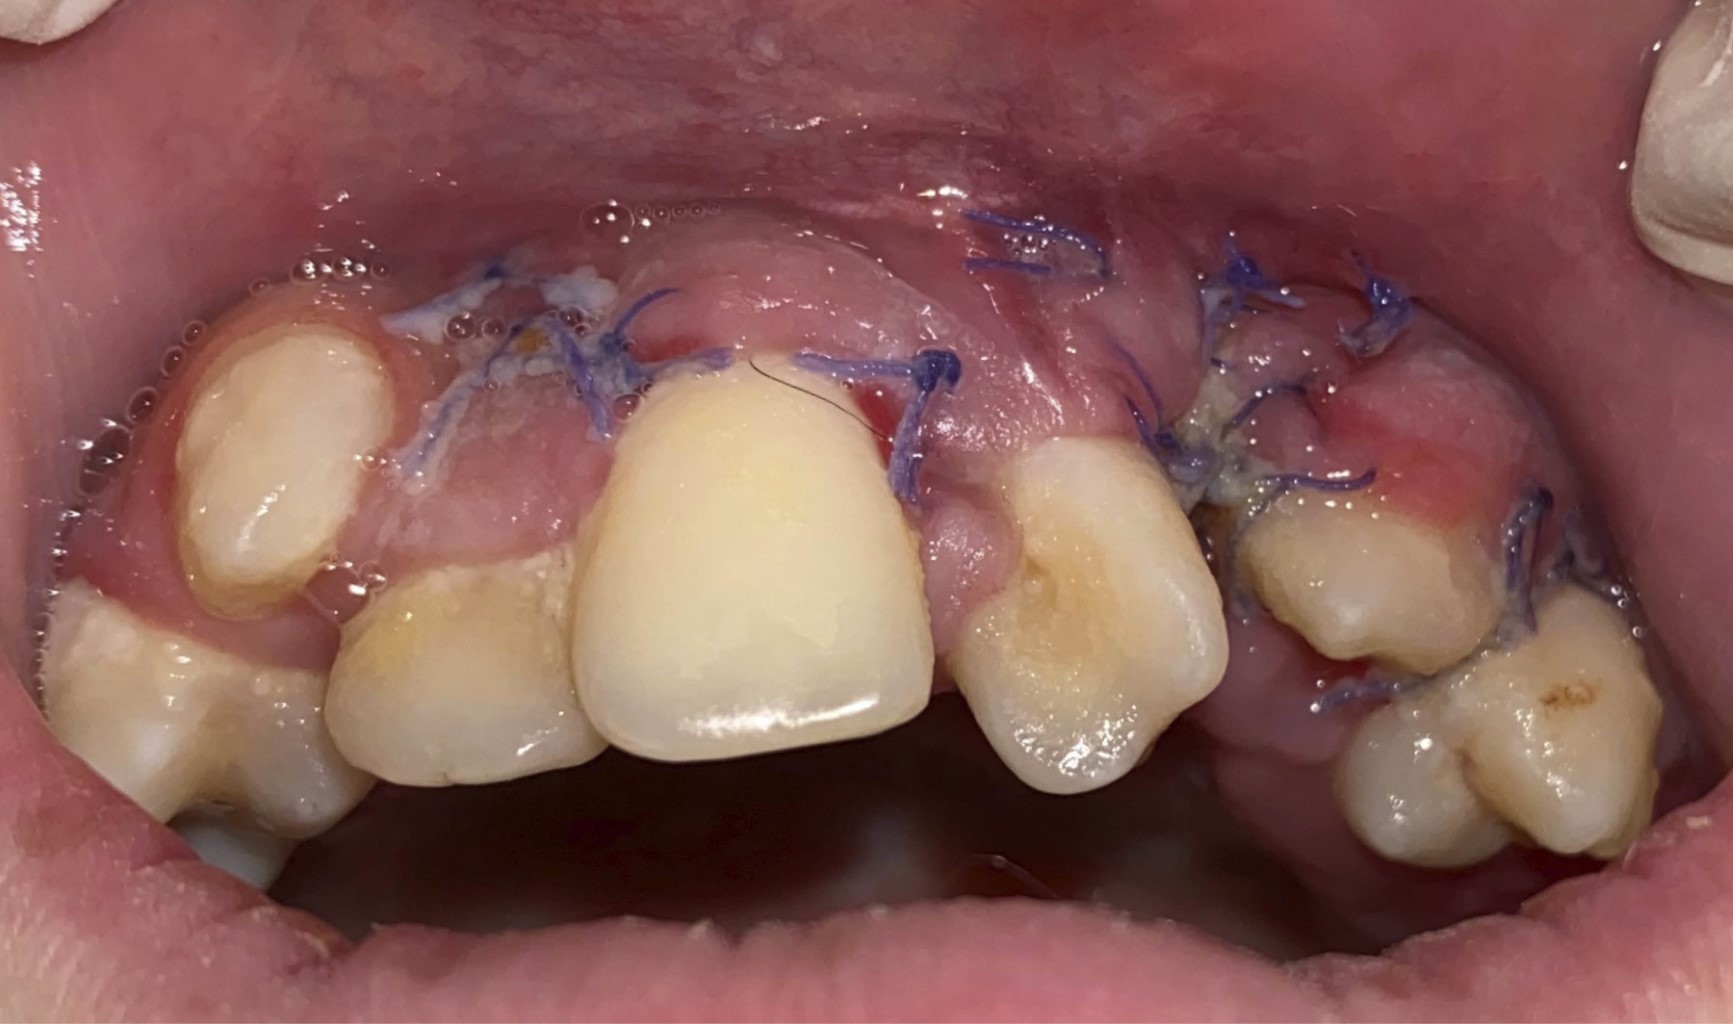

Figure 1

Figure 2

Figure 3

Figure 4

Figure 5

Figure 6

Figure 7